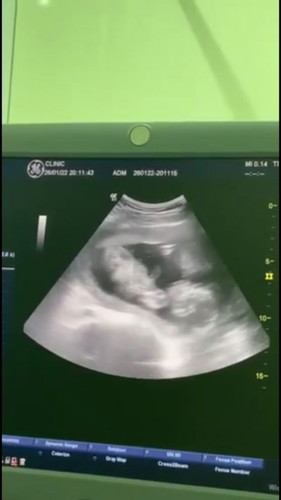

น้องนอนแบบนี้ปกติมั้ยคะ มีคนทักว่าน้องหัวต่ำ ตอนนี้19 w ขอสอบถาม แนะนำหน่อยคะ ทำไมหัวต่ำกว่าตัวคะ

ปกติค่ะเดี๋ยวเขาดิ้นไปดิ้นมาก็จะเปลี่ยนท่าไปเลื่อยๆคะแม่ บ้านนี้เคยนอนคว่ำหน้ามาแล้วค่ะไม่ต้องกังวลนะคะแม่